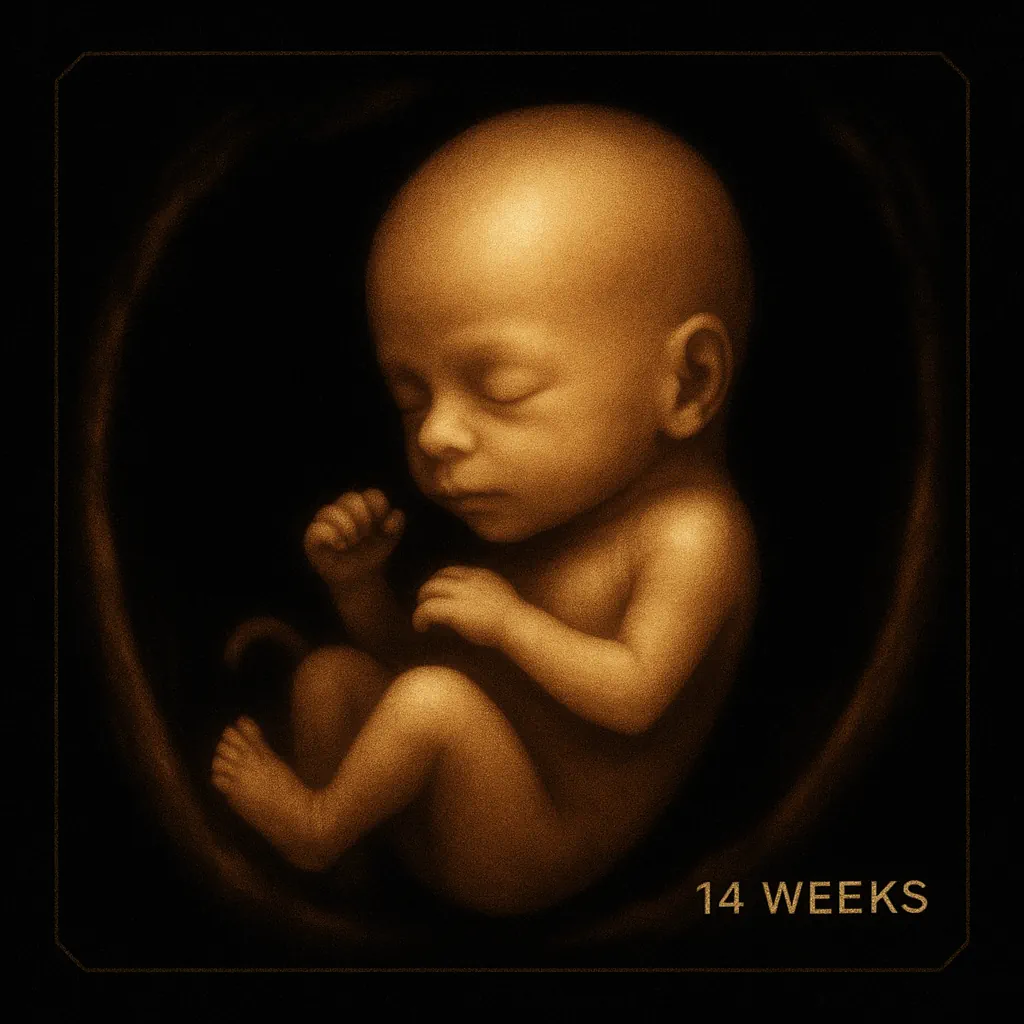

🧠 Physical Growth of the Baby

By week 14, your baby is about the size of a lemon, measuring approximately 2.8 to 4 inches (7–10 cm) in length and weighing around 2 ounces (56 grams).

At this point, your baby’s body is fully formed, and spontaneous movements inside the uterus have begun — even though you can’t feel them yet.

The arms and legs are lengthening, and your baby can move their fingers and toes.

The nervous system continues to develop rapidly, allowing for more coordinated movements.

The neck is now visible, and the head is no longer resting on the chest.

The eyes and ears are moving toward their final positions, giving the face a more human-like appearance.

Fine lanugo hair begins to cover the baby’s skin, helping regulate body temperature. The thyroid gland starts producing its own hormones, supporting healthy metabolism and growth.

Your baby moves hundreds of times a day — stretching, bending, and even sucking their thumb — though you won’t feel it yet. The eyelids remain closed and won’t open until around week 23.

Hair, eyebrows, and eyelashes are beginning to form, and the thyroid hormones are now active, ensuring continued organ growth and energy regulation.